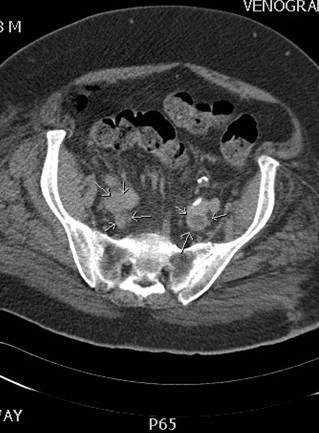

Venografía axial por CT donde se muestra un trombo agudo que va del filtro de VCI  hasta la vena ilíaca interna y externa derecha y la vena ilíaca común izquierda.

Venografía coronaria por CT donde se muestra un trombo agudo que va del filtro de VCI hasta la vena ilíaca interna y externa derecha y la vena ilíaca común izquierda.